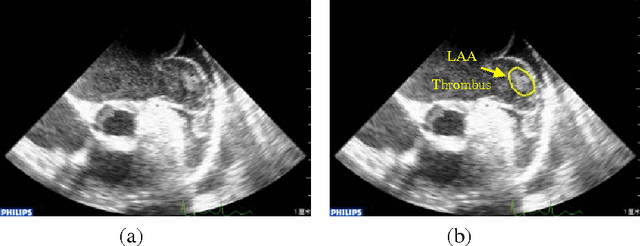

Transesophageal echocardiography (TEE) is widely used to detect left atrium (LA)/left atrial appendage (LAA) thrombi. In this paper, the local binary pattern variance (LBPV) features are extracted from region of interest (ROI). And the dynamic features are formed by using the information of its neighbor frames in the sequence. The sequence is viewed as a bag, and the images in the sequence are considered as the instances. Multiple-instance learning (MIL) method is employed to solve the LAA thrombi detection. The experimental results show that the proposed method can achieve better performance than that by using other methods.